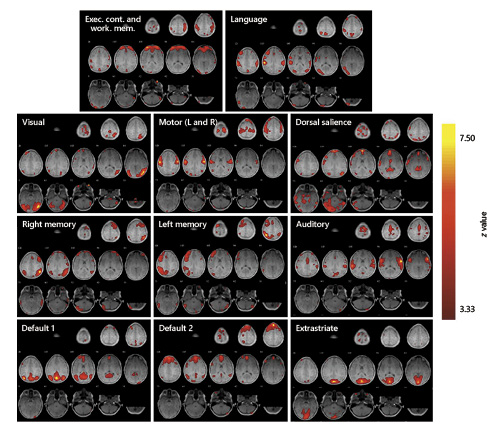

In order to mirror the animal networks obtained and to verify the consistency of the methodology followed in this study, the same analysis was performed on a human sample following the same methodology (Fig. 2). The group-level ICA yielded 11 networks of interest: 1 executive function network (in which WM and EC were merged); 1 language network; 1 visual network; 1 motor network; 1 dorsal salience network; 2 memory networks (left and right); 1 auditory network; 2 default-mode networks; and 1 extrastriate network. Different components were projected onto T1 axial of the first subject.

Resting-state networks in humans. Networks are presented overlaid on axial slices of a human’s brain. Data was calculated with the same methodology as that in Figure 1. The networks shown are executive control and working memory (merged), visual, ventral salience, dorsal salience, right and left memory, audition, default parts 1 and 2, extrastriate, and motor (left and right). The pseudo-colored scale indicates levels of statistical significance.

The main difference in the resting-state networks obtained was that the executive networks of the monkeys (EC and WM) were separated into two components and merged for the human group. Although memory networks are not addressed in this study, it is important to point out that another difference found was that Ateles only has one memory network, while the human group has two memory networks (Fig. 1, 2 and online suppl. Table S1; see www.karger.com/doi/10.1159/000499177 for all online suppl. material).

The following pattern was found, which is involved in the EC and WM networks [Beckmann et al., 2005; Damoiseaux et al., 2006]. The network emerges at the level of the dorsal border of the hemispheres in paracentral regions, predominating on the right side (Fig. 2, WM-EC, 1). There is also a correlation between the central and upper regions, at the level of convexity, with the right side predominating (Fig. 2, WM-EC, 2), and, discretely, in the middle parietal region of the convexity, it predominates on the right side and a portion of the precentral area (Fig. 2, WM-EC, 3). There is discrete connectivity in the medial parietal region (Fig. 2, WM-EC, 4, 5), and a bilateral cluster in the frontopolar, frontobasal, and anterior cingulate areas, up to the knee of the corpus callosum without including it, going slightly above it (Fig. 2, WM-EC, 5–8). In both occipital poles, predominating on the right side, a discrete correlation is observed (Fig. 2, WM-EC, 8–10). Components are also observed in the cerebellum, particularly on the right side and at the junction with the anterior and lateral faces (Fig. 2, WM-EC, 11, 12). Similar components were found to those observed in healthy humans in the literature [Biswal et al., 1995; Raichle et al., 2001; Hampson et al., 2002; Greicius et al., 2003; Beckmann et al., 2005; Damoiseaux et al., 2006], consistent with what was found in Ateles (Fig. 3, 4), confirming the hypothesis of a possibly related WM system in spider monkeys.